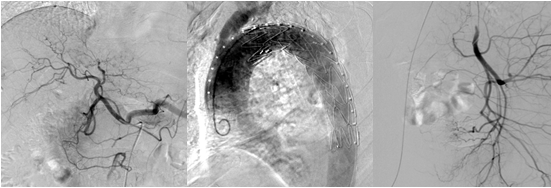

1.3 數(shù)字減影血管造影DSA

數(shù)字減影血管造影是上世紀(jì)80年代繼CT之后出現(xiàn)的將電子計(jì)算機(jī)與常規(guī)X線血管造影相結(jié)合的一種新檢查方法。近年來(lái),選擇性動(dòng)脈造影得到廣泛應(yīng)用。DSA影像的形成是基于數(shù)字熒光成像DF,其影像形成過(guò)程與傳統(tǒng)的利用X線成像相同,即透射成像。